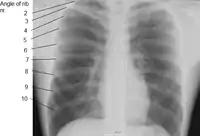

Las costillas humanas generalmente son 12 a cada lado (24 en total): 7 verdaderas o esternales (I-VII), 3 falsas o asternales (VIII-X), y 2 flotantes (XI y XII), en forma de arco con un cuerpo con dos caras, externa e interna; dos bordes, superior e inferior; y dos extremos, posterior y anterior.

- Ángulo: La separación entre el ángulo y el tubérculo es progresivamente mayor de la segunda a la décima costillas. La porción entre el ángulo y el tubérculo es redonda, áspera e irregular, y sirve para la inserción del músculo dorsal diente vértebra torácica; falta este tubérculo en los últimos 3 pares de costillas.